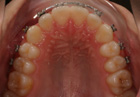

Soggetto con III classe dento-scheletrica! Perdita di spazio per caduta precoce di 5.3 ed inclusione del 1.3; si e' deciso di eseguire una terpia ortodontica di tipo fisso con prescrizione MBT - apertura dello spazio; opercolectomia della gengiva a livello del 1.3 - trazione con filo dritto spessore .012NiTi in bassa frizione! Il caso viene mostrato nella fase della finitura prima dello sbandaggio ed a fine terapia!. Durata: 26 mesi; Inizio Novembre 2005 - Fine Gennaio 2008